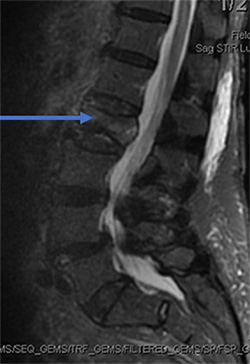

88 year old female fell in the bathroom with increasing amount of back pain. Despite pain pills in the hospital, she could not get out of bed. MRI showed compression fracture due to osteoporosis (weak bone). MRI can show if the fracture is new based on swelling in the bone. The arrow shows the bone is whiter than the other bones indicating a new fracture.